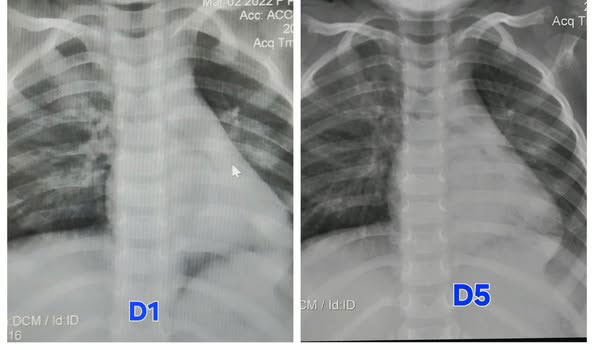

តាមប្រភពមន្ទីរពេទ្យគន្ធបុប្ជា បានឱ្យដឹងនៅរសៀលថ្ងៃទី២២ ខែតុលា ឆ្នាំ២០២៥ ថា កុមារីអាយុ៣ឆ្នាំ មកពីខេត្តកំពង់ស្ពឺ ដោយមានជំងឺរលាកសួត បណ្តាលមកពីវីរុសគ្រុនផ្តាសាយបក្សី H5N1 ត្រូវបានសង្គ្រោះជីវិត ហើយថ្ងៃនេះ (ថ្ងៃទី២២ ខែតុលា ឆ្នាំ២០២៥) កូនស្រីបានវិលត្រឡប់ទៅផ្ទះវិញ ដោយស្នាមញញឹម ជាមួយពុកម៉ែ។